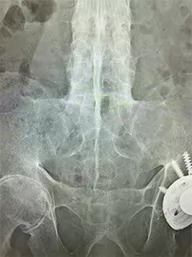

Vol.05[腰背部痛]

中学生の頃から腰背部痛が出現し、初めは日中に運動で軽減されることもあったが、最近は継続的に痛みがあった。痛みとともに首から腰の可動域が制限されることがあり背中が硬く感じた。近医でNSAIDsが処方されて長期に内服しているが症状は改善せずに持続し、原因不明の腰背部痛として当院紹介となった。